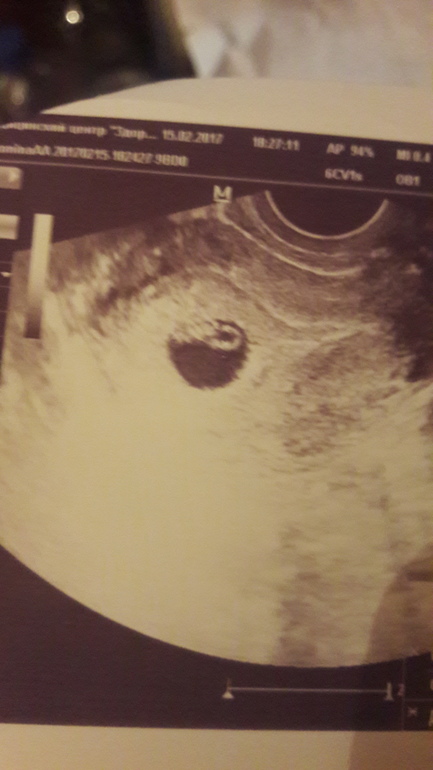

Привет девочки!!! Позавчера сижу на обеде и как схватило бок левый. Я бегом в клинику звонить. Записей нет((( я в трубку реву... соединили с врачем,сказала чтоб презжала пол шестого. Всю трясет как осиновый листочик. Презжаю...ложусь на кушетку...врач говорит: "маточная беременность. Видишь пульсирует?" А я ничего не вижу в голове только маточная беременность!!! И тут она звук включает. Сердечко!!! Слезы счастья сами текут!!!

Наша первая фотосессия

На узи позавчера. Срок по месячным 6+4.

Срок 6,4 по месячным. Я особо не вникала в размеры. Главное, что гиня сказала ,что хорошо развиваемся и соответствуем сроку.

Вы про пол? Он 7 мм, невозможно что то увидеть))